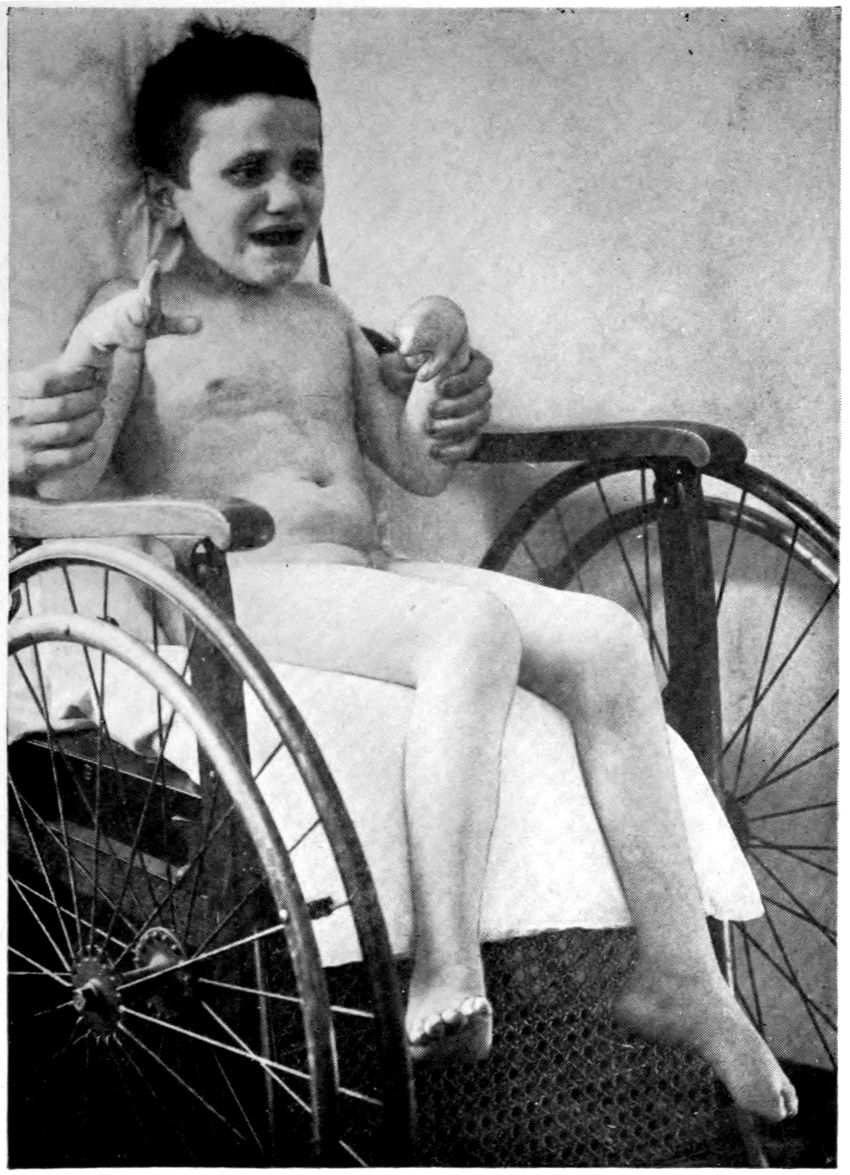

JUVENILE PARETIC NEUROSYPHILIS (“juvenile paresis”). Autopsy.

Case 5. John Lawrence was an under-sized negro, who came under hospital observation when he was 23 years of age. There was some evidence that the patient’s father was a neurosyphilitic although accurate data were out of the question. At all events, John had Hutchinsonian teeth, a forward bowing of the tibiae, and Argyll-Robertson pupils. These findings together with a history of backwardness at school seem to stamp the diagnosis. It seems that there had been a change for the worse from the age of 18, though the boy had been able to sell newspapers and black shoes up to within a year of his arrival at the hospital. During the last months of his life, he showed a general incoördination, with false movements suggesting those of a drunken person. There were numerous tremors, the glance was shifting, and there was a tendency to nystagmus. Some of these phenomena (taking into account that the Hutchinsonian teeth were not entirely typical and there was even at times some doubt as to whether the pupils were actually stiff) led to a question of the diagnosis multiple sclerosis.

There was, however, little doubt that the case was one of juvenile paresis. Among the symptoms found at various times in this case are the following: disorientation for time, place and persons, confusion, with coarsely irrelevant replies to questions, ill-defined and transitory delusions of persecution, auditory, tactile, and visual hallucinations, and defective memory.

Early in life, the patient had had a habit of falling asleep in school hours, and had experienced a number of falls at various times. During an attack of measles he had had a number of spasms, each of which lasted ten minutes or more.

The autopsy showed death to be due to an early bronchial pneumonia. The thymus was persistent, measuring 3 × 2 × .5 cm. The marrow of the femur was red.

46There was a moderate degree of sclerosis of the aorta confined to a few plaques in the arch (not a characteristic syphilitic scarring of the aorta). The spleen was small and had a thickened capsule.

The majority of the lesions, however, were in the nervous system, and the following description is taken from the routine hospital records to exemplify the findings in a fairly characteristic case of Juvenile Paresis.

Head: Scalp closely adherent to calvarium. Calvarium heavy without diploë. Dura adherent to calvarium in bregmatic region. Sinuses contain liquid blood. Arachnoidal villi in considerable quantity. Pia mater contains considerable clear fluid and shows diffuse haziness and focal thickenings. The diffuse haziness is almost universal and is best marked over the superior surface of the cerebellum. The focal thickenings are of general distribution over the veins of the sulci on the superior surface of the brim and are heaped up to form considerable linear mounds near the region of the arachnoidal villi. The superior surface of the cerebellum is traversed by similar linear mounds of fibrous tissue running at an angle to the laminæ. There is no notable increase of fibrous tissue at the base.

Brain: Weight 965 grams. The sulcation is roughly symmetrical except in the occipital poles where there is unusually rich and complex but shallow sulcation. The cortical substance is everywhere firmer than normal, but the sulci fail to flare notably. In a few places there is a focal increase of consistence of still greater degree with apparent local hypertrophy (or gliosis with increase of substance). These foci are in the right second temporal gyrus (3 cm. in diameter) and in the left first temporal gyrus (of same size but somewhat less firm) and are of a whitish, waxen appearance, being visible several feet away by reason of their color and apparent encroachment upon the adjacent sulci. The foci are sharply limited by the sulci laterally, but pale out gradually before and behind.

The convolutions of the vertex show another type of lesion. The tissue of the greater part of the vertex resembles that of the flanks and base in being firmer than normal and of a grayish pink color. Behind the fissure of Rolando on the right side and behind the anterior limits of the ascending frontal region on the left 47side the brain tissue of the vertex becomes suddenly still firmer and of a yellowish gray color. This lesion disappears gradually into the occipital microgyria behind and the gyri gradually lose their yellowish tint. The lesion fades away gradually so that it fails to involve the temporal convolutions.

The cerebral tissue cuts firmly and smoothly. The tissue of the frontal region is a little edematous. The white matter is of a normal appearance. The ependyma of all the ventricles is somewhat sanded. The fourth ventricle is most affected.

The cerebellum is not edematous and is as firm as the normal olivary bodies. The cerebellar hemispheres are symmetrical and of a normal appearance, save that the laminæ are slightly narrower than usual and very compactly set. The color, where not obscured by the haziness of the pia mater, is of a grayish pink somewhat suggestive of freshly tanned shoe leather. The substance cuts smoothly and firmly. The dentate nuclei are unusually firm. The pons is small, but of the usual color. Lower structures normal except the cord which is small and shows curious deviations from the normal markings. The posterior horns and gray commissure are at many levels the only structures to preserve the normal gray appearance, so that the H or butterfly appearance is replaced by a crescent. At these levels, traces of gray matter often stand out in the loci of the anterior horns.

The important anatomical diagnoses in the nervous system are as follows:

Atrophy of cerebrum, 965 grams (there is of course a question whether we are not dealing with a degree of cerebral hypoplasia).

Focal scleroses of cerebrum, suggesting the tuberous scleroses of Bourneville.

Occipital microgyria.

Cerebral and cerebellar gliosis.

Chronic ependymitis.

Gliosis of the gray matter of the spinal cord.

Chronic diffuse and focal leptomeningitis.

The microscopic examination confirmed the diagnosis of paresis. The hypertrophic nodules were of special interest. 48They were found to be overlain by a characteristic though thin exudate of lymphocytes and plasma cells, together with pigmented cells. The nodules appeared to be supplied with an unusual number of vessels of small calibre, about which were a few lymphocytes. The large vessels and those with well developed adventitiæ were surrounded by more numerous lymphocytes and by more focal accumulations of pigmented cells. The cortex in the middle of a nodule had almost lost its characteristic cortical layering. The cortex was here reduced (specimen from temporal lobe) to about one-quarter of its normal thickness, and was found to be composed largely of expanded neuroglia cells and vascular tissue, with a few nerve elements, small, shrunken, and dark-staining. The destructive process appeared to have borne hardest on the layer of internal large pyramids and the fusiform layer. There was, however, nowhere any evidence of focal necrosis such as ought to characterize a true gumma. The sections stained by the Marchi method failed to show evidence of fatty degeneration within the focus, although there was a marked diffuse accumulation of fatty granulations along the nerve fibres in the underlying white matter. A special study of the cerebellar material was made by one of the authors.[4] Occasional Purkinje cells showed the characteristic binucleate condition, which has frequently been noted in recent literature.

The cerebellum of this case was perhaps the most markedly diseased of all portions of the nervous system. As noted, the cerebellar tissue was exceedingly firm. How far the notable incoördination of the case (he was observed on staff rounds characteristically curled up in a heap, showing quite an unusual degree of general incoördination) was due to the cerebellar lesions, it is perhaps not possible to say.

Summary: John Lawrence, Juvenile Paretic Neurosyphilis, is a foil to Case 3 (James Dixon), paretic neurosyphilis due to acquired syphilis.

Both showed Cerebral Atrophy, but Lawrence the more 49markedly because of hypoplasia incidental to the congenital origin of his condition.

Whereas Dixon gave little or no sign of stigmata, Lawrence (besides being under-sized, having suspicious teeth, and showing at autopsy a persistent thymus) showed a Hydromyelia and curious trefoil shape to the spinal cord. Dixon on the other hand had liver lesions and arterial lesions of the leg.

The suggestion of Tuberous Sclerosis in Lawrence is not found in Dixon; but we have not found it elsewhere. Bourneville did not describe tuberous sclerosis as syphilitic.

Binucleate Purkinje cells emphasize the congenital source of the lesions in Lawrence.